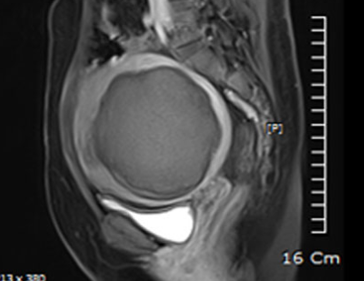

• 시술 전

시술 후